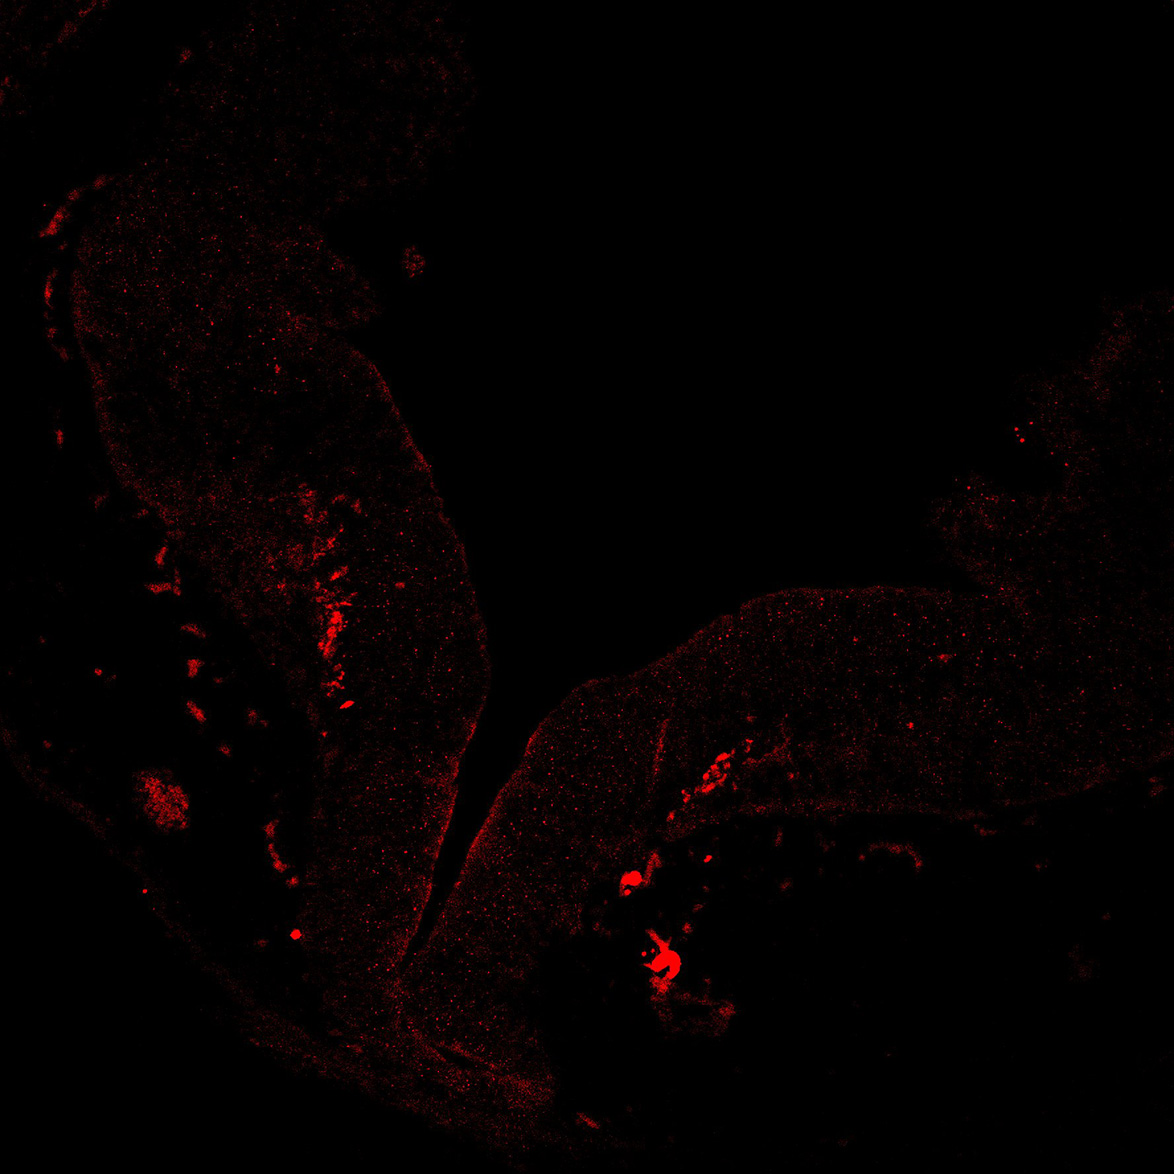

TH

19PCW human midbrain